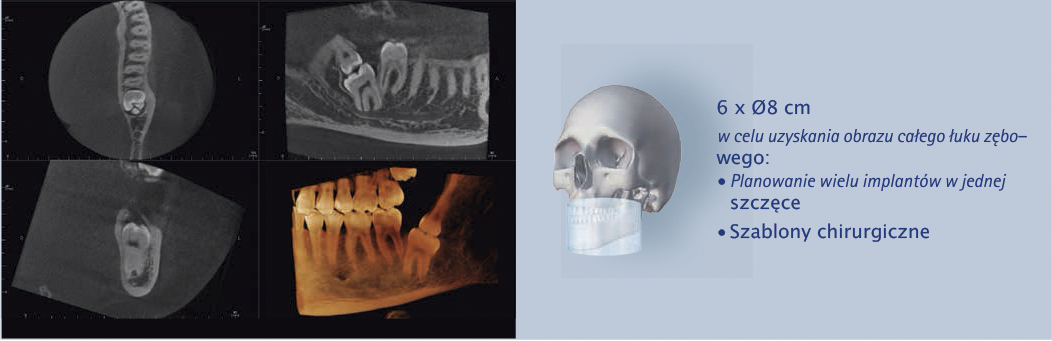

Cztery różne pola obrazowania zapewniają niezawodną diagnostykę 3D w całym obszarze jamy ustnej. Zapewniają one precyzyjne dopasowanie, odpowiednie do wskazań a także uniwersalne możliwości zastosowania w codziennej praktyce – od endodoncji, poprzez implantologię do chirurgii jamy ustnej.